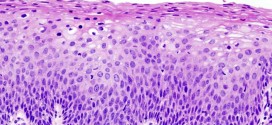

Leer MásNEOPLASIA VULVAR INTRAEPITELIAL

La neoplasia vulvar intraepitelial. Ver cáncer de ovario. Si fuese de su deseo le podemos elaborar un plan trofológico personalizado para usted.

Leer MásLEUCOPLASIA MALIGNA VULVAR

La leucoplasia maligna vulvar. A pesar de la accesibilidad de la región vulvar tanto en la exploración clínica como en la obtención de las muestras citológicas, los conocimientos de su patología neoplásica maligna y de lesiones precursoras son muy inferiores a los que se han obtenido en otras estructuras del aparato genital femenino. La incidencia de esta neoformación ha aumentado …